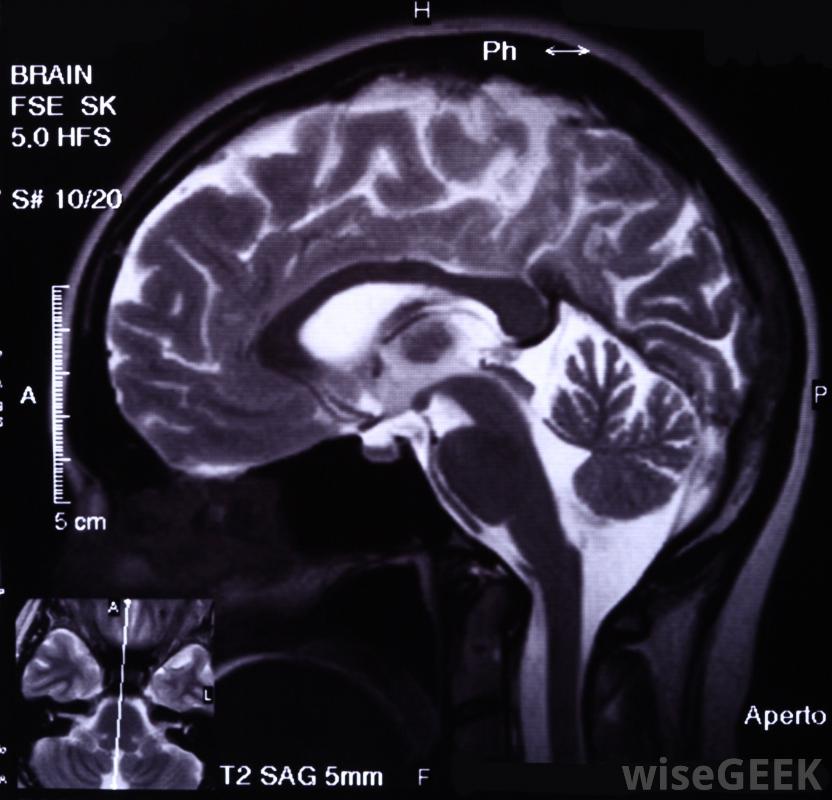

圖像引導用于確定腦內支架的放置。

一些曾經中風的人的風險可能會增加如果放置了腦支架,圖像引導對于放置大腦支架至關重要,以確保支架位于正確的位置。此外,醫生可能會要求進行血管造影研究,以跟蹤血液在大腦中的流動情況。這可以讓醫生確認支架已正確放置并且工作正常。如果不是這樣,可能需要進行后續程序來解決這種情況